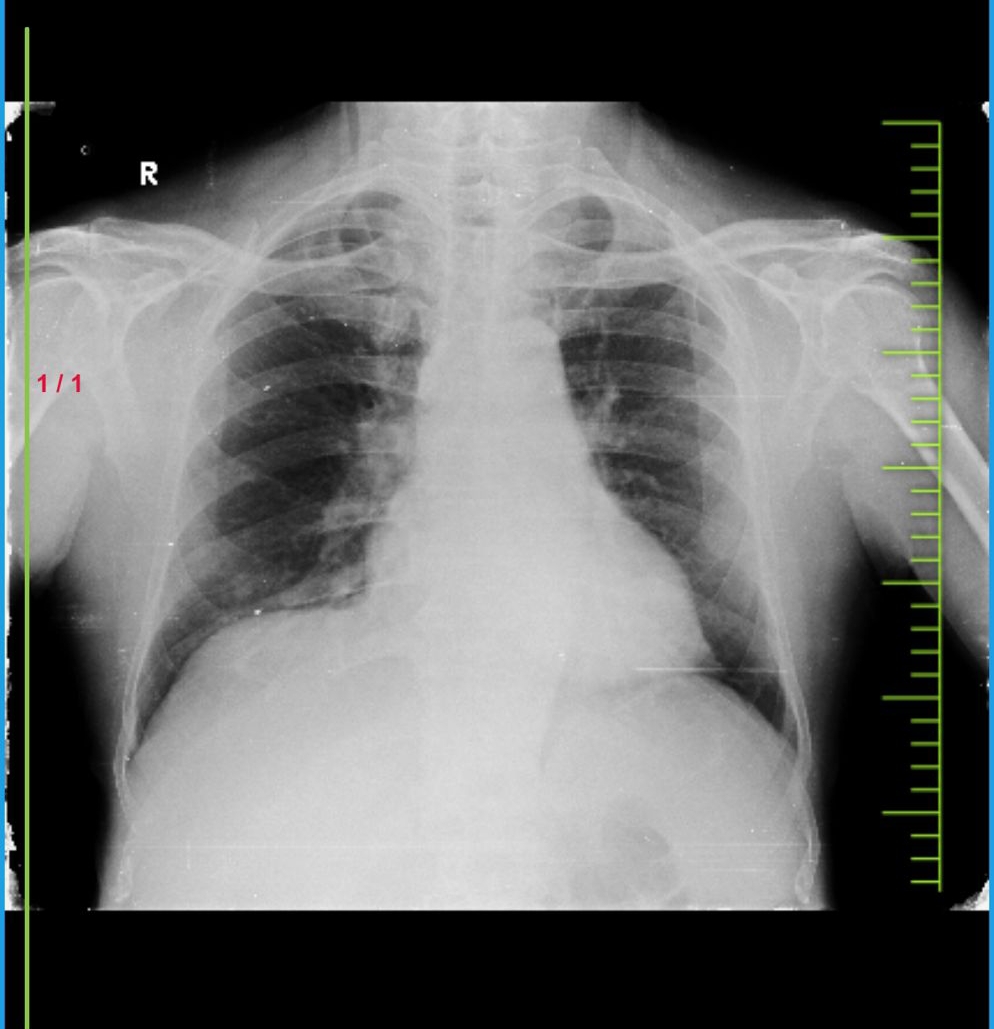

CHEST XRAY:

8/2/24